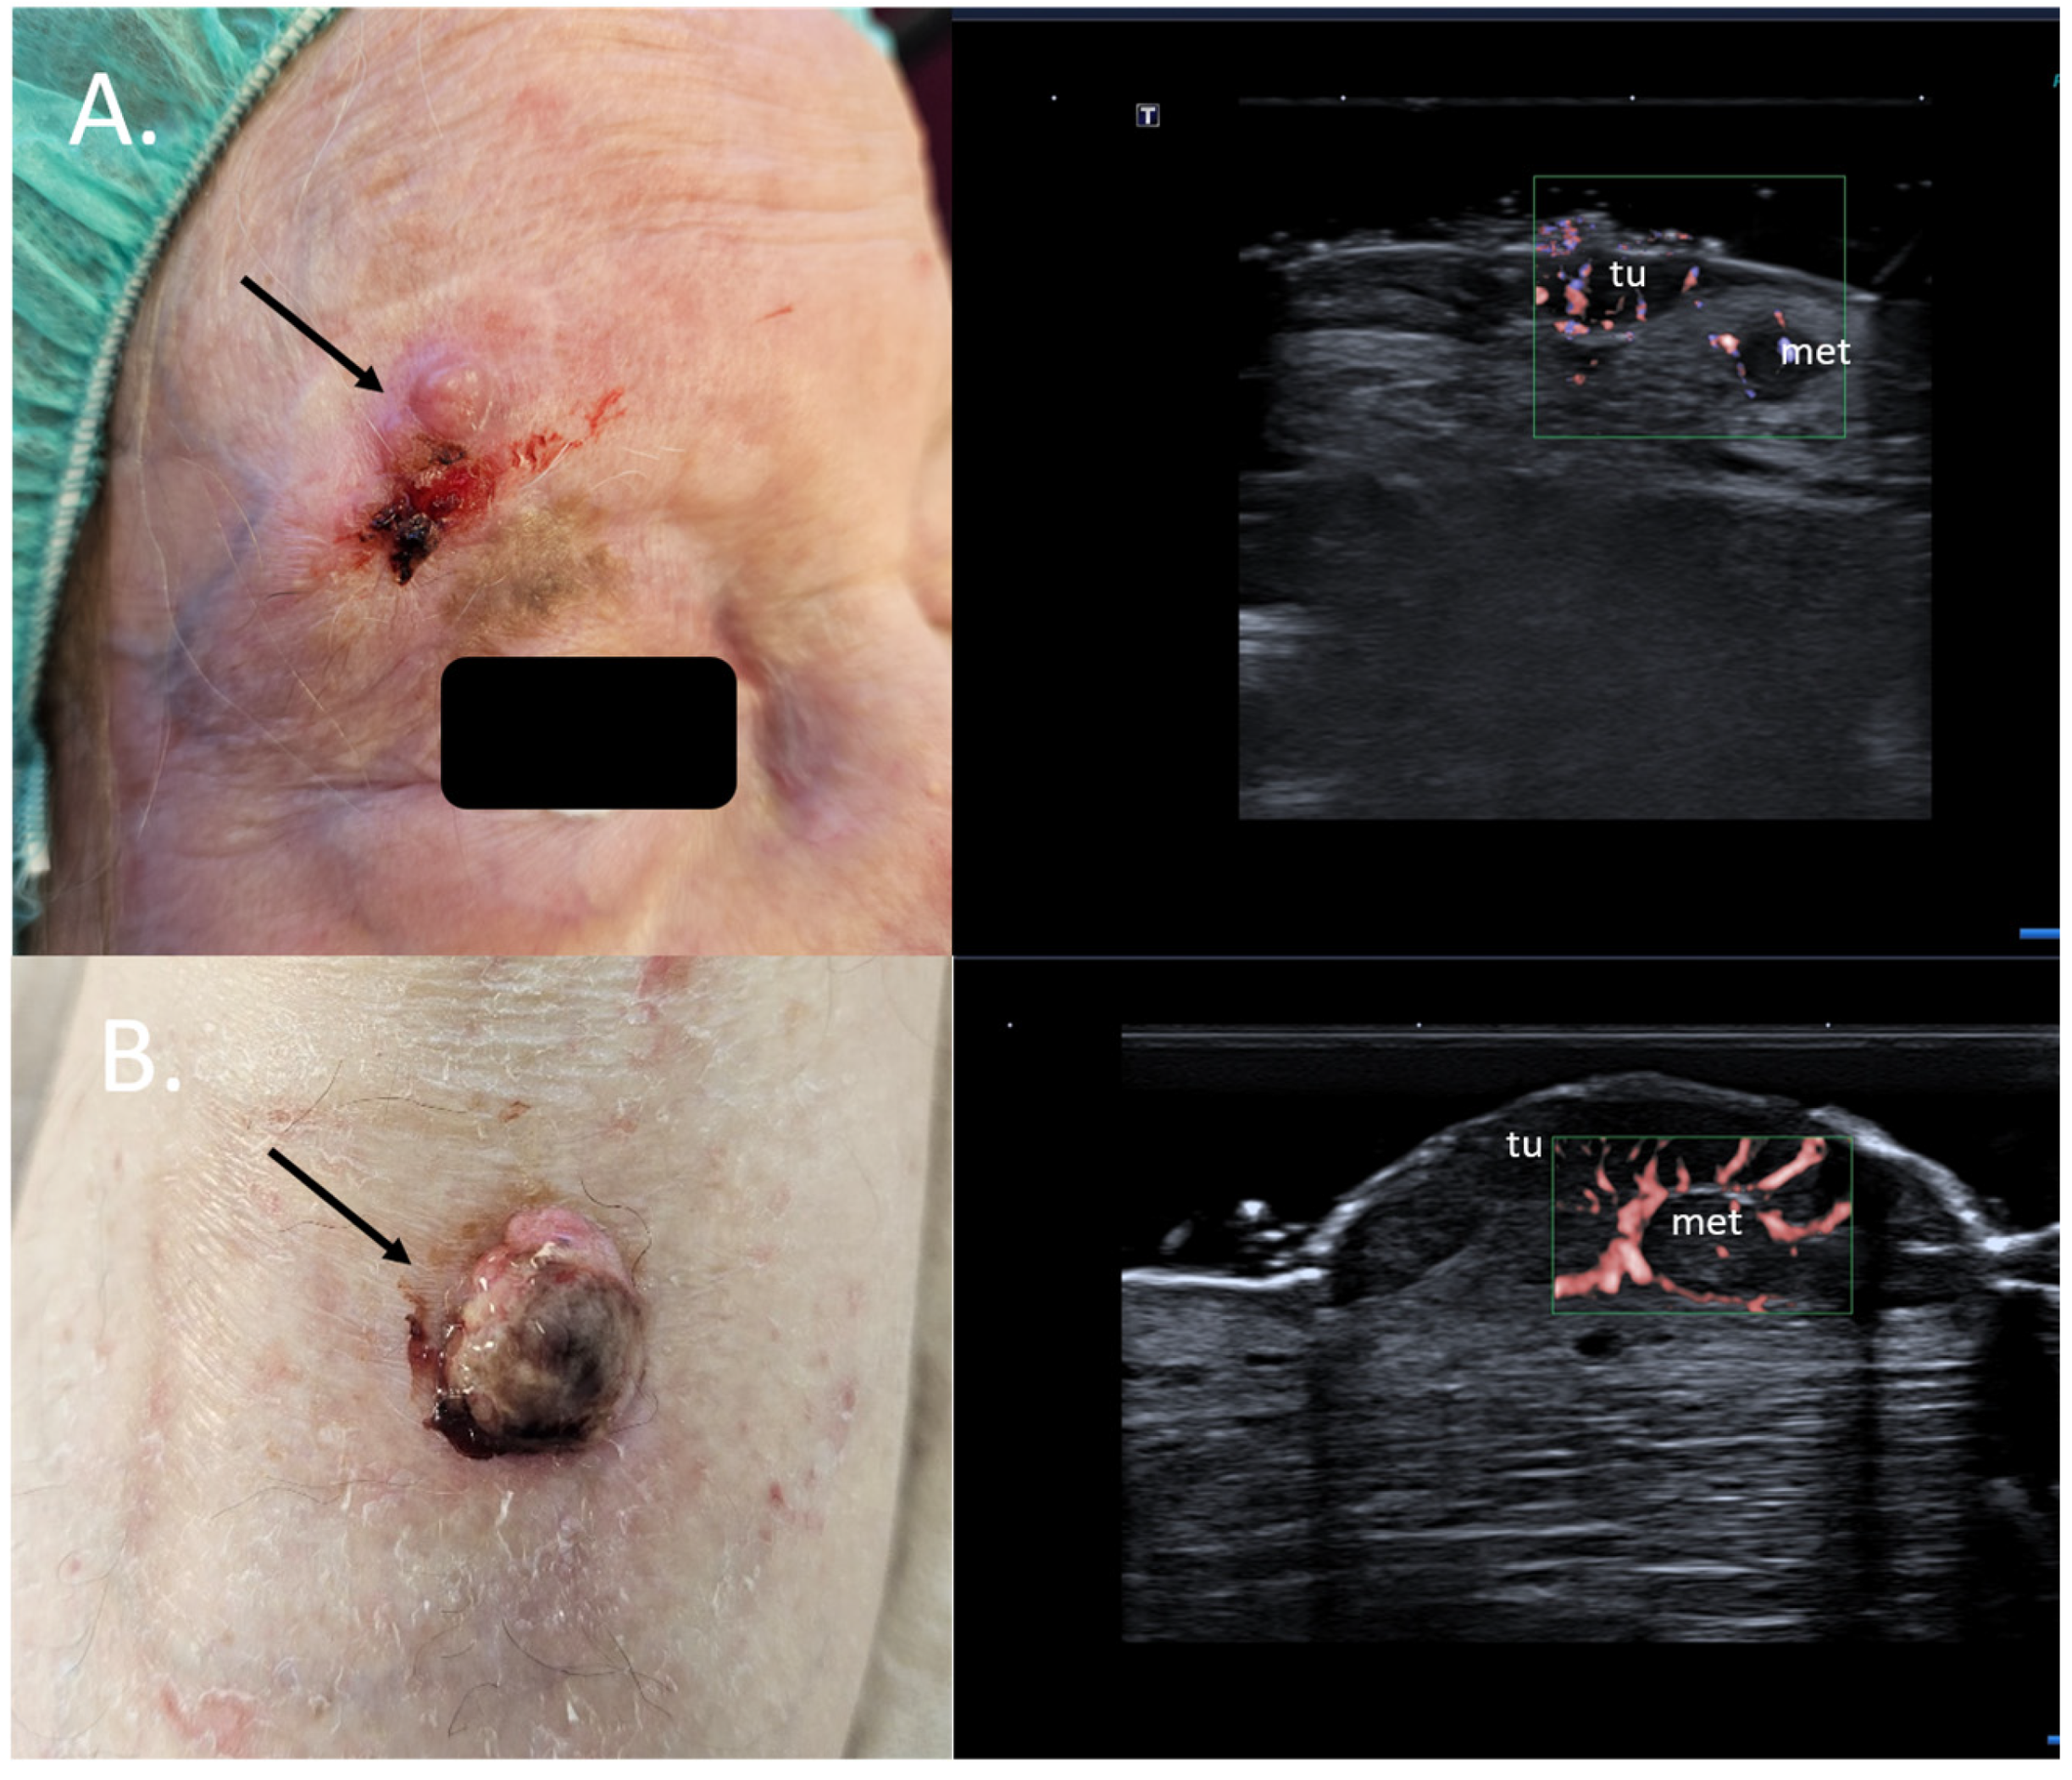

2. Enhancement of Diagnostic Accuracy, Avoidance of Misdiagnosis, Early Identification of Local Relapse

- Catalano, O.; Crisan, D.; Díaz, C.P.G.; Cavallieri, F.; Varelli, C.; Wortsman, X. Ultrasound Assessment of Skin Tumors Local Recurrence. J. Ultrasound Med. 2023, 42, 2439–2446. [Google Scholar] [CrossRef]